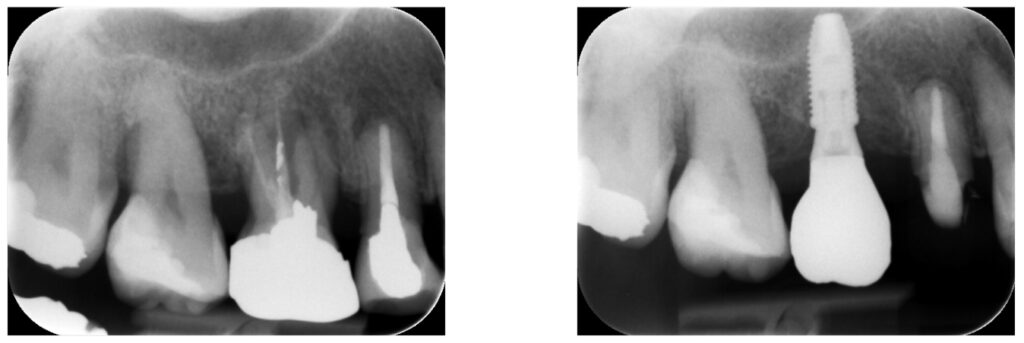

インプラントを埋める

歯ぐきを切開し、穴を作り人工歯根を顎の骨に埋め込んでいきます。

その後、インプラントと骨が結合するのを待つため、2~3か月ほど待期期間となります。

骨としっかり結合したのを確認し、アバットメントを装着

次に二次処置アバットメント取付作業になります。

骨と結合しているのを確認して、インプラントにアバットメントを装着します。